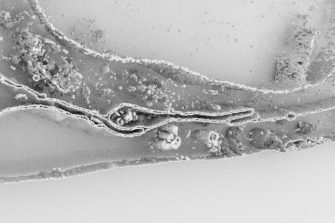

Interactive cell exploration

In 2016, an interactive virtual reality cell environment, the first of its kind, was generated at the 3D Visualisation Aesthetics Lab. The prototype uses the latest room-scale virtual reality technology and high-resolution electron microscopy data to allow researchers to observe the processes by which nanoparticles carrying cancer therapies are internalised and trafficked within a cancer cell. It is anticipated that this work will shift the paradigm of education while accelerating the science discovery process by offering researchers novel perspectives on drug delivery. Initial assessment of the learning outcomes of immersive media education compared with traditional screen-based methods in undergraduate students suggests VR can improve learning but further work is needed.

Watch a video flythrough of the VR cell environment

Based on ground-breaking research being undertaken by scientific collaborators at the Monash Institute of Pharmaceutical Science (MIPS) and the University of Queensland (UQ), the 3DVAL developed a thought-provoking computer-generated animation describing the stages of novel nanoparticle drug delivery to cancer cells isolated in the laboratory. The sequence incorporates accurate high-resolution microscopy data of a breast cancer cell and structural data from the Protein Data Bank to enhance scientific authenticity.